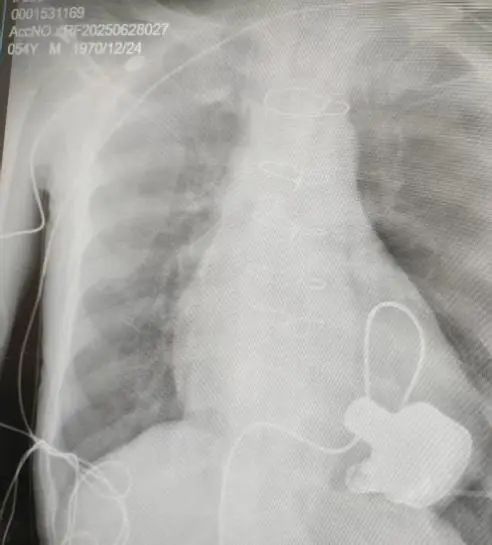

術后影像